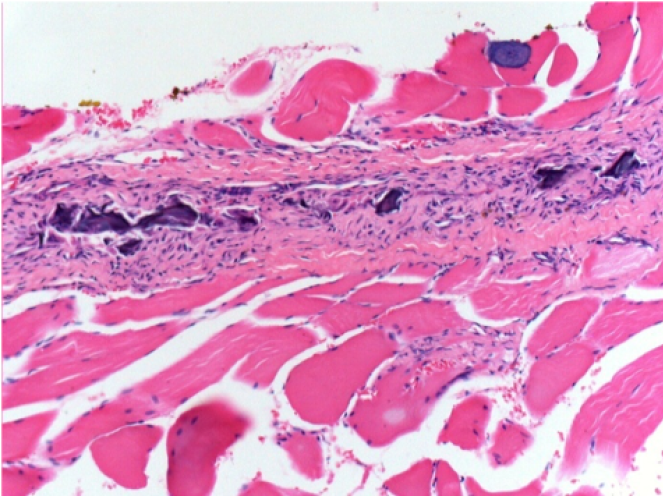

07

1 month after Endopeel Injection

1 month after Endopeel Injection 0.1ml in the right pretibial muscle.

What is seen in black on the pictures is not a necrosis like could imagine some scientifics !

In fact, 4 conclusions have to be taken in consideration

- an artefact of coloration

- an absence of necrosis

- an apoptosis

- a bioregenerative process

L : Control-100xD30

R:100xD30

R :400xD30